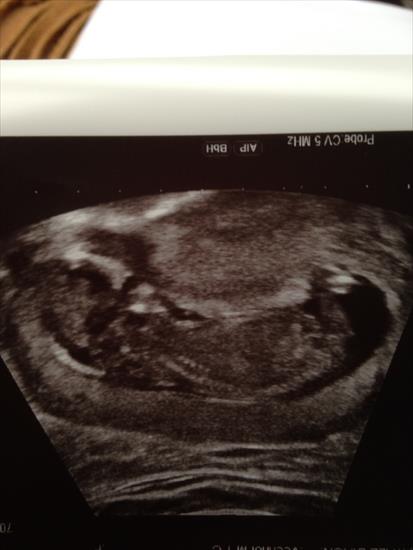

I am 13.4 weeks pregnant on this picture!